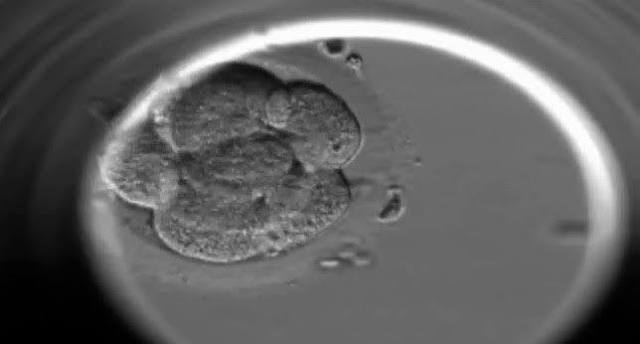

Nace en Gran Bretaña el primer bebé probeta, engendrado mediante fertilización artificial o "in vitro".